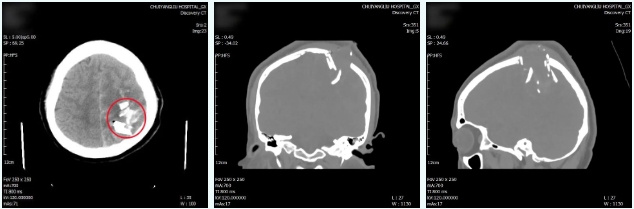

近日,北京市垂杨柳医院神经外科成功救治1例复杂颅脑损伤患者。该患者由警察送来医院时为昏迷状态,左顶部创口活动性出血,伴有脑组织、脑脊液外溢,情况危急。医院急诊外科在接诊后急查头CT显示左顶部凹陷性粉碎性骨折,多块骨折碎片插入脑组织中。患者病情危在旦夕,急诊外科紧急联系神经外科会诊。

▲术前急诊的CT检查显示多块骨折碎片刺入脑组织中